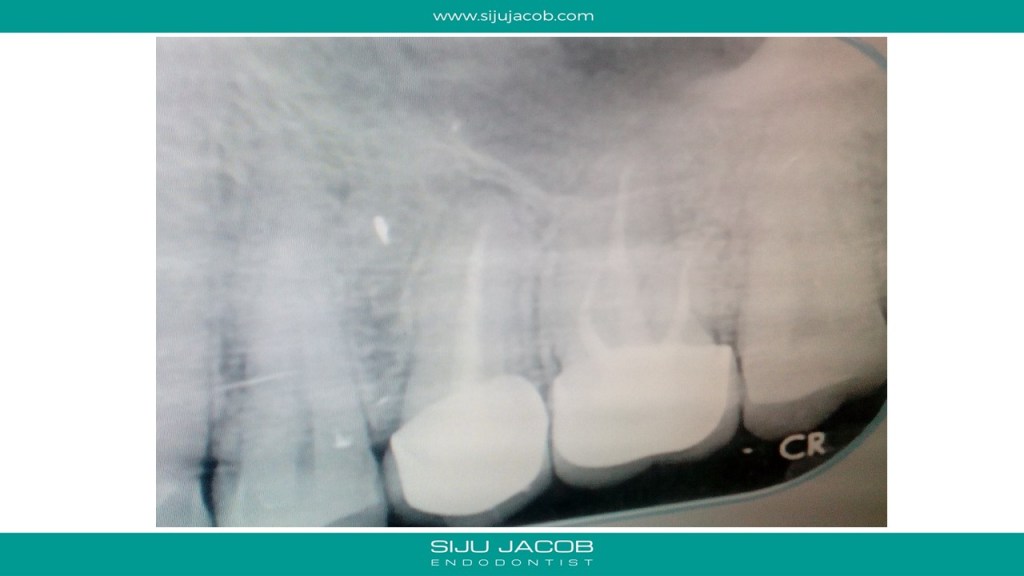

This patient mailed me saying that she had pain in the area where 2 teeth were root canal treated and crowned. She then sent me this radiograph.